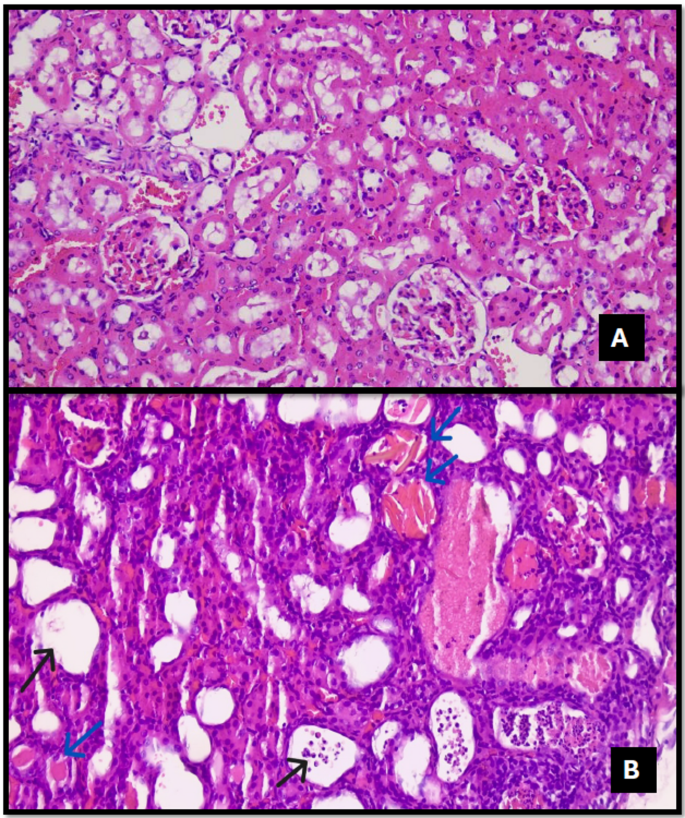

In the control group, renal structures were consistently within normal morphological limits across all histopathological examinations, with no evidence of inflammation, necrosis, or degeneration (Figs. 1, 2, 3, 4, 5, 6, 7, 8 and 9).

Tubular dilation (Fig. 7) was observed in 16.7% of the Control (SF) group, 50% of the DEX group, 87.5% of the TAC group, and 100% of the TAC + DEX group. A statistically significant difference was detected among the groups (p = 0.003) (Table 3).

Loss of the brush border (Fig. 8) was observed in 87.5% of the TAC group and 100% of the TAC + DEX group. A statistically significant difference was detected between the groups (p = 0.019) (Table 3).

Cast formation (Fig. 9) was observed in 87.5% of the TAC group and 25.0% of the TAC + DEX group. A statistically significant difference was detected between the groups (p = 0.020) (Table 3).